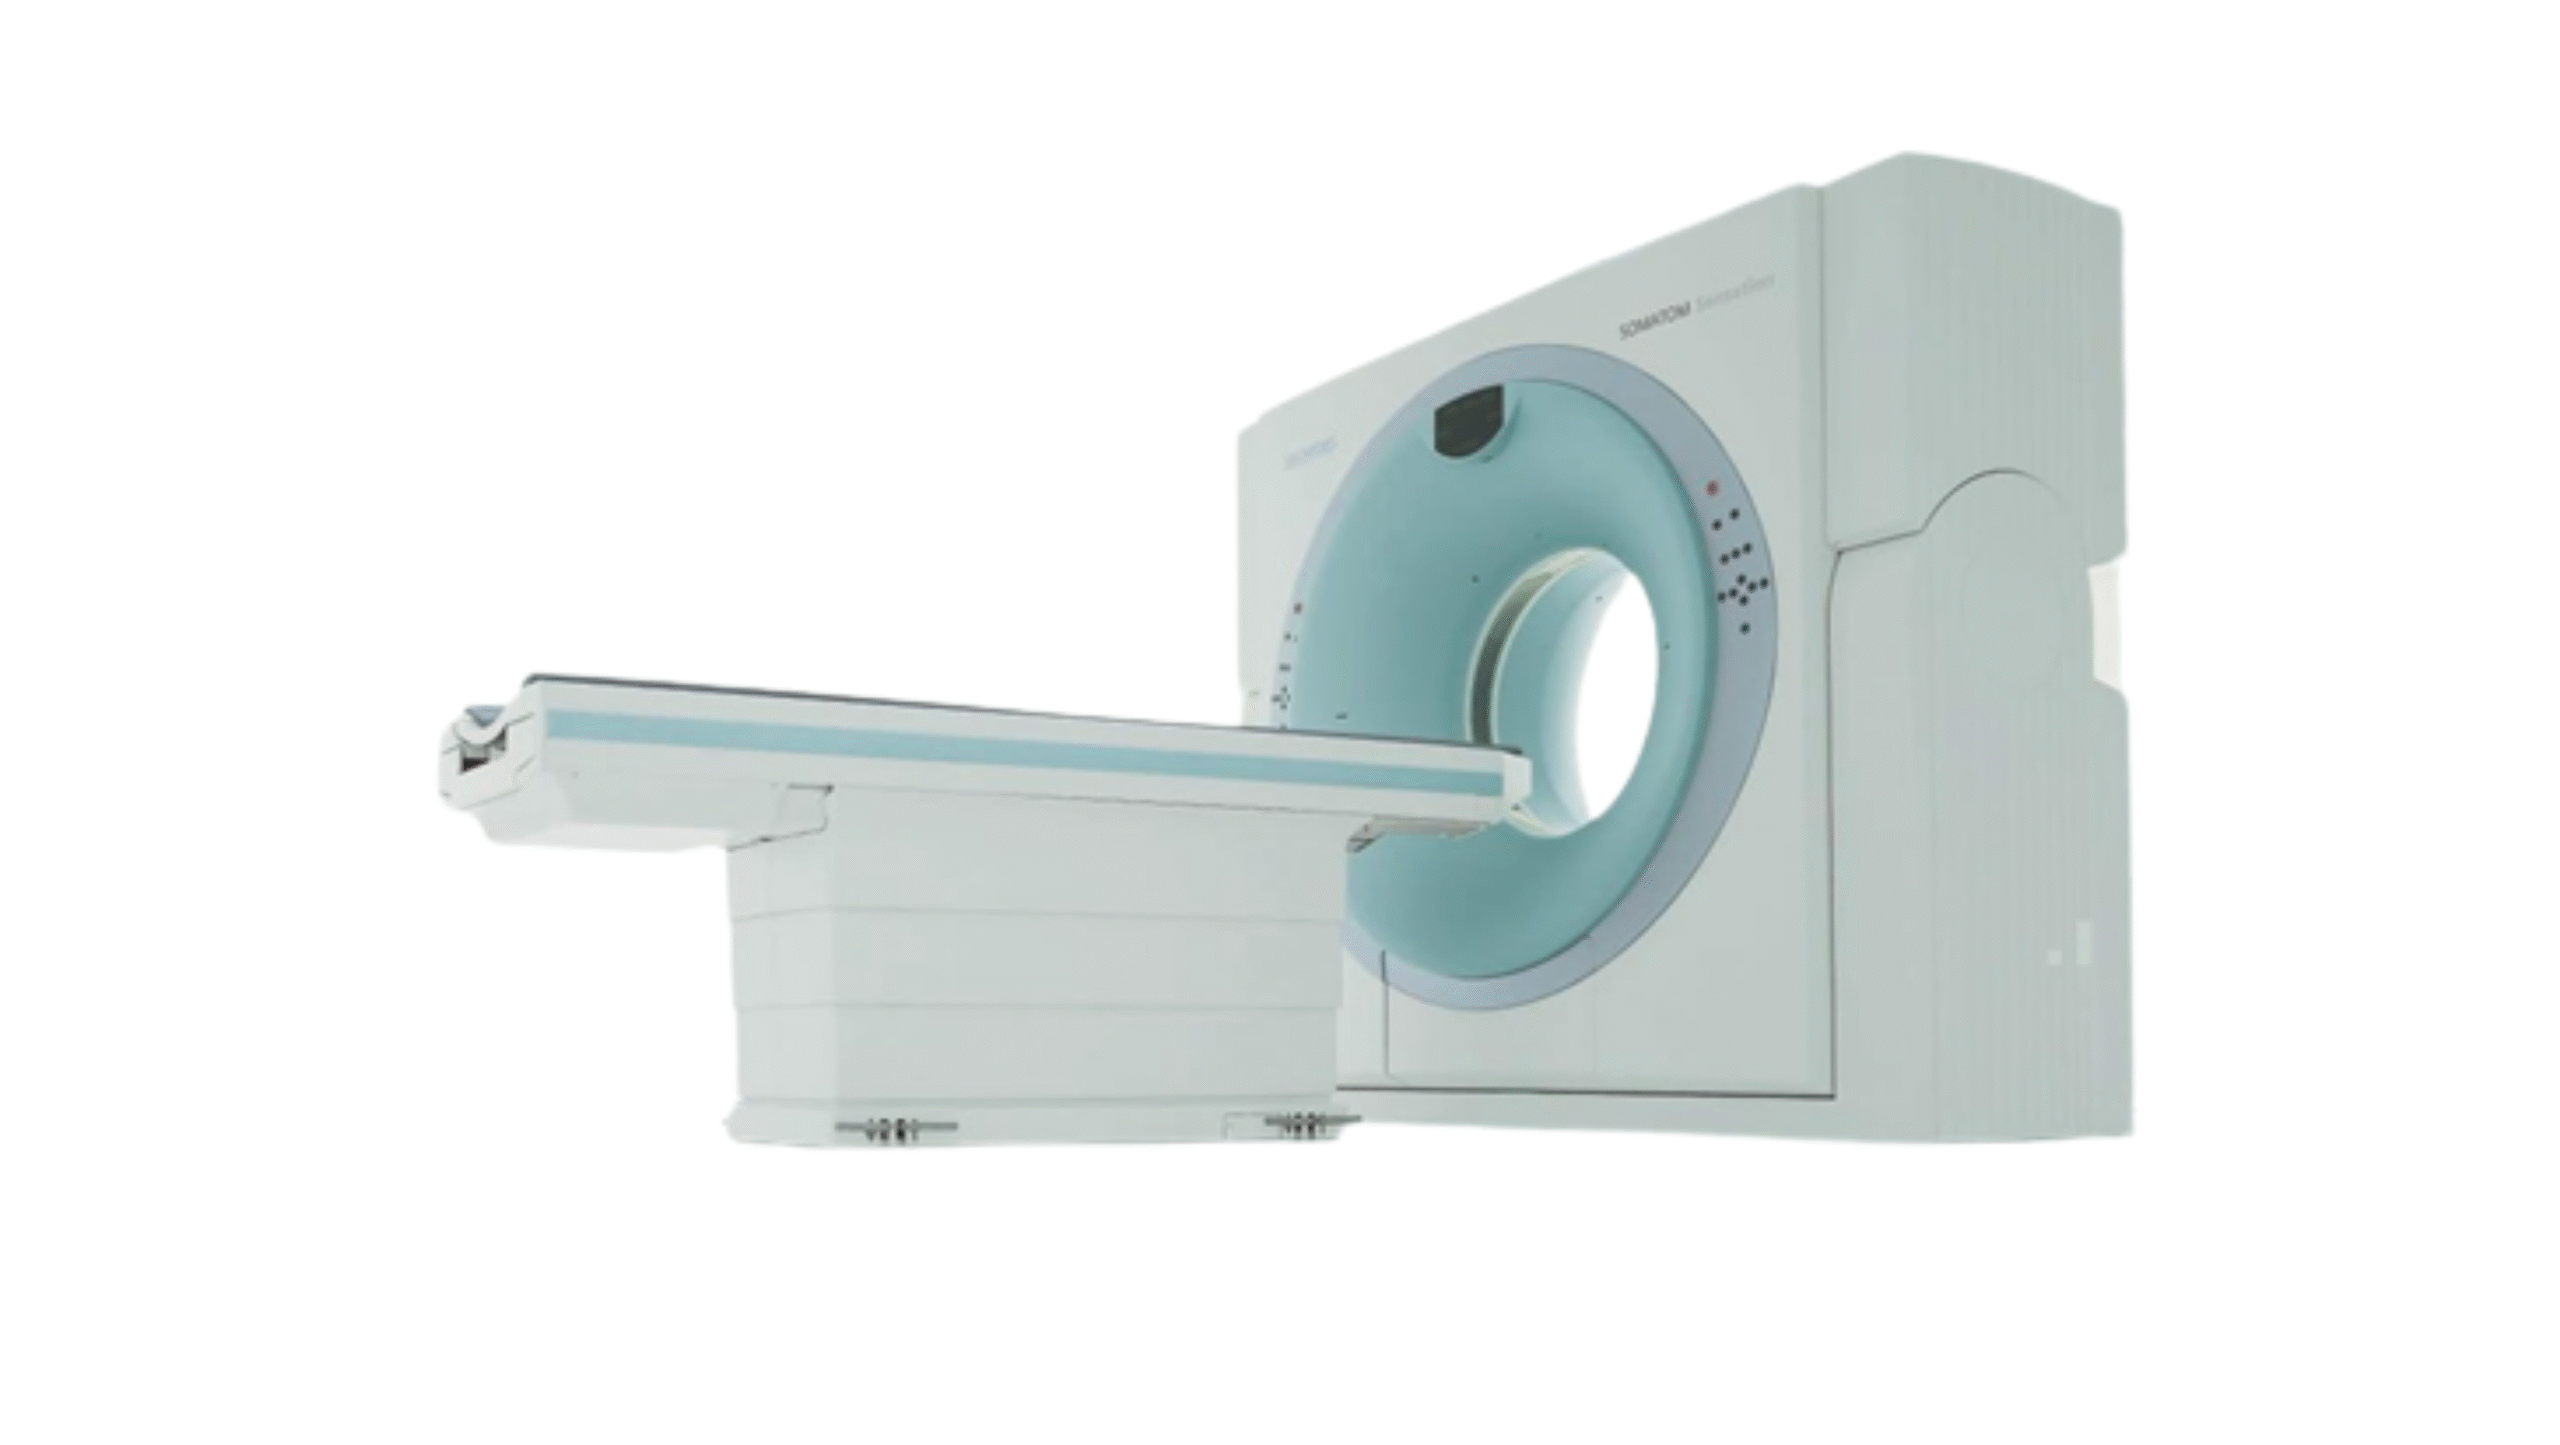

Products